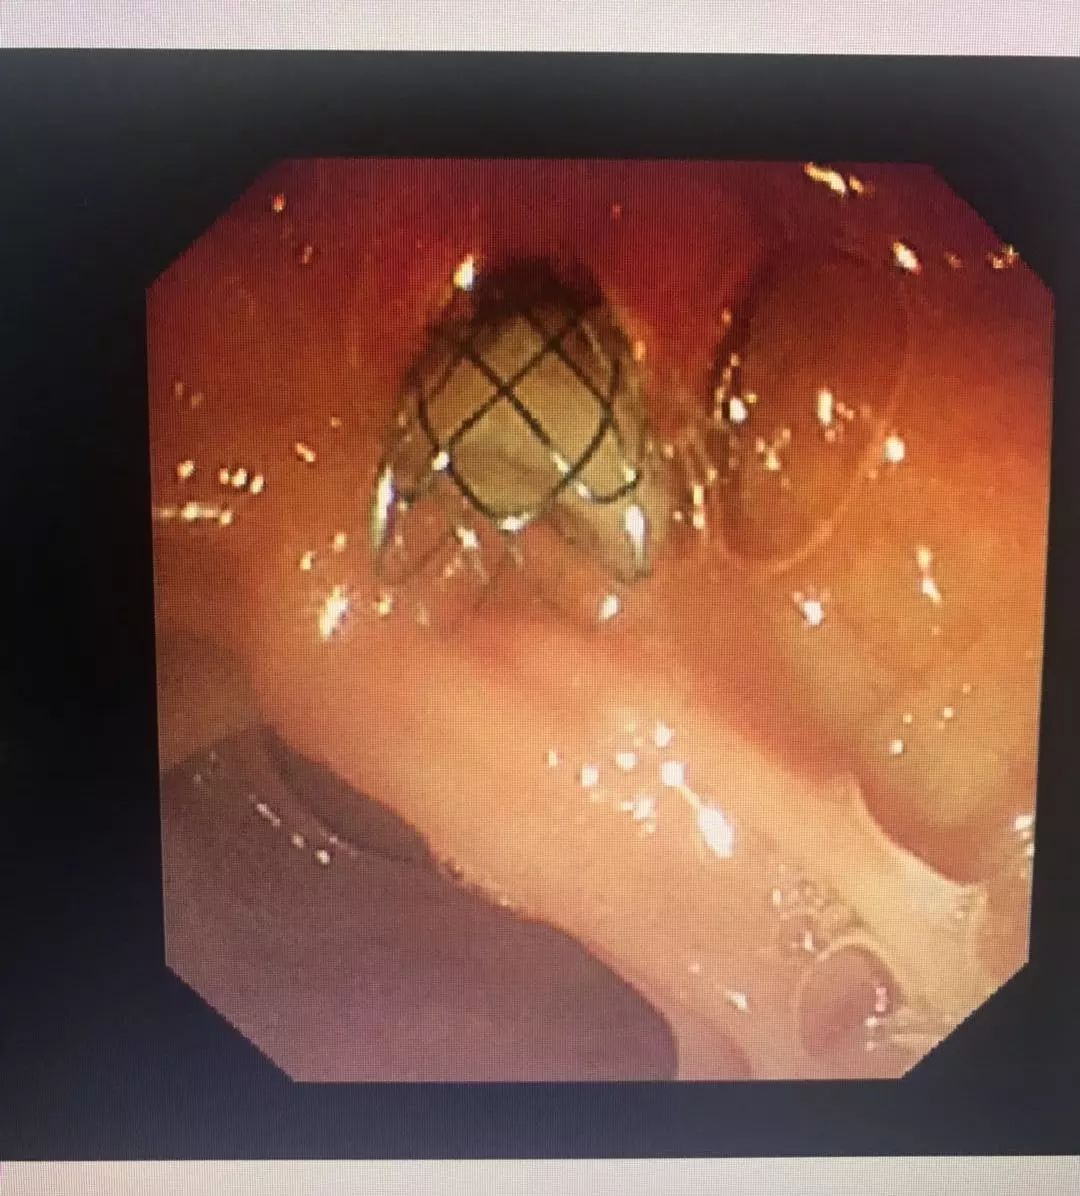

沿11点方向切开十二指肠乳头约0.3 cm,见墨绿色胆汁涌出。保留导丝,经导丝置入一8mm×60 mm无覆膜胆道金属支架,支架下端位于乳头开口下方1.0 cm处,支架上端过狭窄段约2cm,见有大量脓性胆汁涌出。内镜操作顺利,麻醉满意,未出现出血,穿孔、胰腺炎等并发症。

内镜示:肠内支架引流脓性胆汁

造影示:支架位置良好